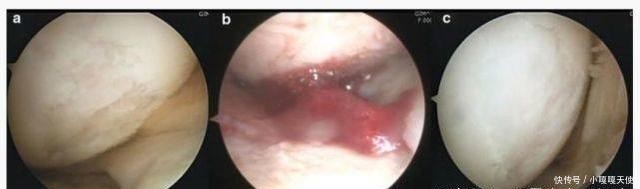

摘要:近年来,随着老龄化人数的增加和健身运动的兴起,半月板损伤的人数急剧增加。半月板啊为膝关节的重要解剖结构,位于胫骨平台与股骨内外髁之间的楔形纤维软骨组织 半月板损伤半

近年来,随着老龄化人数的增加和健身运动的兴起,半月板损伤的人数急剧增加。半月板啊为膝关节的重要解剖结构,位于胫骨平台与股骨内外髁之间的楔形纤维软骨组织